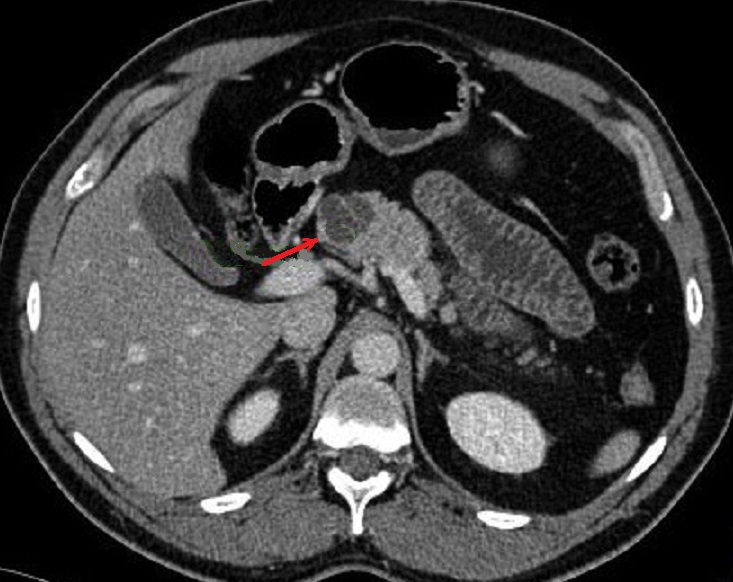

Image radiologique TDM d'une

cystadenome sereux multikystique cephalique du

pancreas a aspect multikystique comporte de plusieur

kyste hypodensite de < 2cm situe a la tete du

pancreas ( fleche rouge ) . Coupe TDM axcilaire |

|

Aspect radiologique du cystadenome

sereux multikystique de la tete du pancreas . La

tumeur est comporte par des kyste a moindre 2cm a

hypodense , de contour et cloison septal interne

sont nette , Image radiologique TDM non contrast

intraveineuese , coupe axiale . |